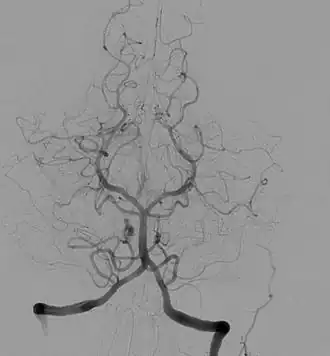

Tętnica podstawna (łac. arteria basilaris) – w anatomii człowieka pojedyncza tętnica powstająca z połączenia obu tętnic kręgowych. Biegnie w bruździe podstawnej mostu, na swoim przebiegu oddając liczne drobne gałęzie, a następnie w dole międzykonarowym dzieli się na tętnice tylne mózgu. Jej gałęzie unaczyniają m.in. płaty potyliczne i skroniowe mózgu, most, móżdżek oraz ucho wewnętrzne. Rozgałęzienie końcowe tętnicy podstawnej jest elementem koła tętniczego mózgu[1][2].

Nieparzystą tętnicę podstawną tworzą obie tętnice kręgowe łącząc się na stoku kości potylicznej[3]. Tętnica biegnie ku górze, pośrodkowo (tylko u 15–25% osób w linii prostej, z wiekiem wygina się bocznie od płaszczyzny pośrodkowej[4]) w bruździe podstawnej mostu, ku jego górnemu brzegowi, gdzie dzieli się na gałęzie końcowe – tętnice tylne mózgu[3]. Jej długość odpowiada wymiarowi powierzchni brzusznej mostu w płaszczyźnie pośrodkowej[5].

Odmianą tętnicy podstawnej jest jej rozdwojenie na krótkim odcinku nazywane wyspą naczyniową[4].